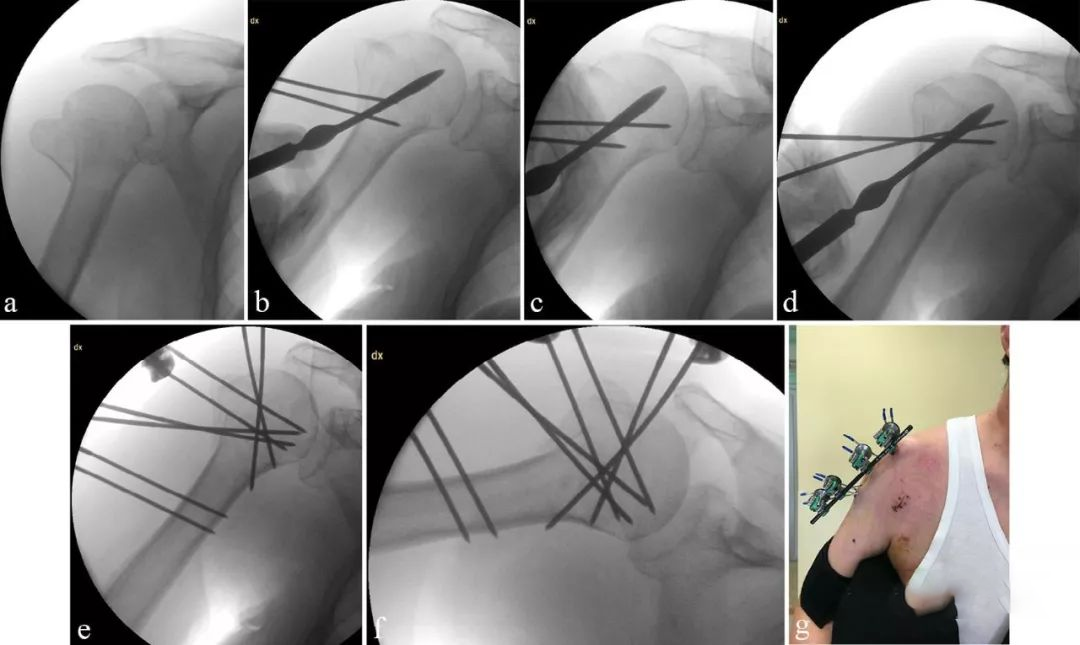

图2 a 61岁男性肱骨近端骨折,b-d在外科颈远端2-3cm处从肱骨外侧皮质置入螺纹克氏针。通过2cm的皮肤切口置入钝剥离子进行骨折复位,复位完成后通过外科颈置入肱骨头。e-f一旦复位成功,就按照框架B进行连接。g框架B外形。术后肩关节15°外展固定悬吊。

图1左:框架A三组钉固定,右:框架B四组钉固定。